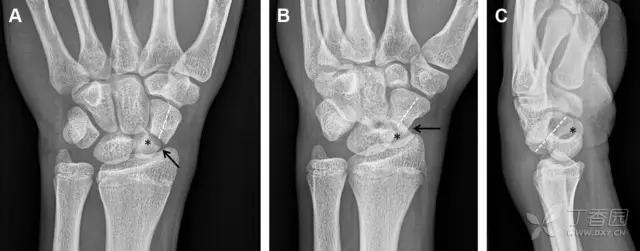

33 腕掌关节骨折脱位

腕掌关节骨折脱位为高能量损伤,常伴有神经损伤。腕掌关节组成骨多,侧位片上重叠遮挡多,骨折不易发现,容易漏诊。在前后位片上,关节面不平滑、关节间隙不对称、关节皮质破坏、关节面重叠常提示腕掌关节骨折脱位。特别是第 4、5 腕掌关节脱位,在前后位片上不容易发现;该损伤不稳定,也称为「变异型拳击手损伤/骨折」。

图 4 第 4、5 腕掌关节骨折脱位。(A)正常腕掌关节,关节面平衡起伏、平行;前后位(B)、斜位(C)、侧位(D),第 5 掌骨近端附近软组织肿胀(白色箭头),冠状面关节面重叠,背侧撞击剪切应力致钩状骨骨折(*),在前后位及斜位片上可见双密度影。第 4 掌骨底部可见微小骨折碎片(D,虚线箭头),第 4、5 掌骨掌侧成角。(E~G)变异型拳击手损伤:第 4、5 掌骨背侧脱位而未见骨折(E,虚线方框),钩状骨有骨折小碎片(F,短虚线箭头),第 4 掌骨基底部关节内骨折(G,长虚线箭头)